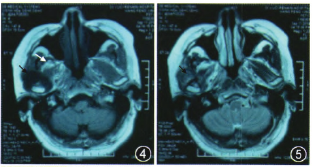

MRI:右顳下領(lǐng)關(guān)節(jié)及顱底可見形態(tài)不規(guī)則結(jié)節(jié)狀,T1稍長、T2不均勻信號(hào)影,間隙增寬,病變邊緣光滑,與周圍組織界限清晰,右側(cè)翼內(nèi)、外肌萎縮。增強(qiáng)掃描病變內(nèi)可見不均質(zhì)中等程度強(qiáng)化。提示:右顳下頜關(guān)節(jié)良性腫瘤(圖4~6)。